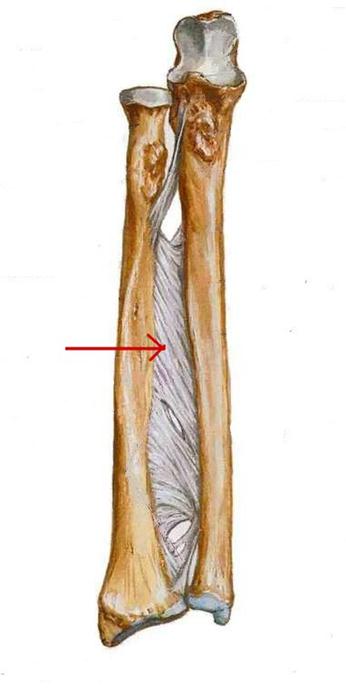

S: Стрелка указывает на...

+:membrana interossea antebrahii